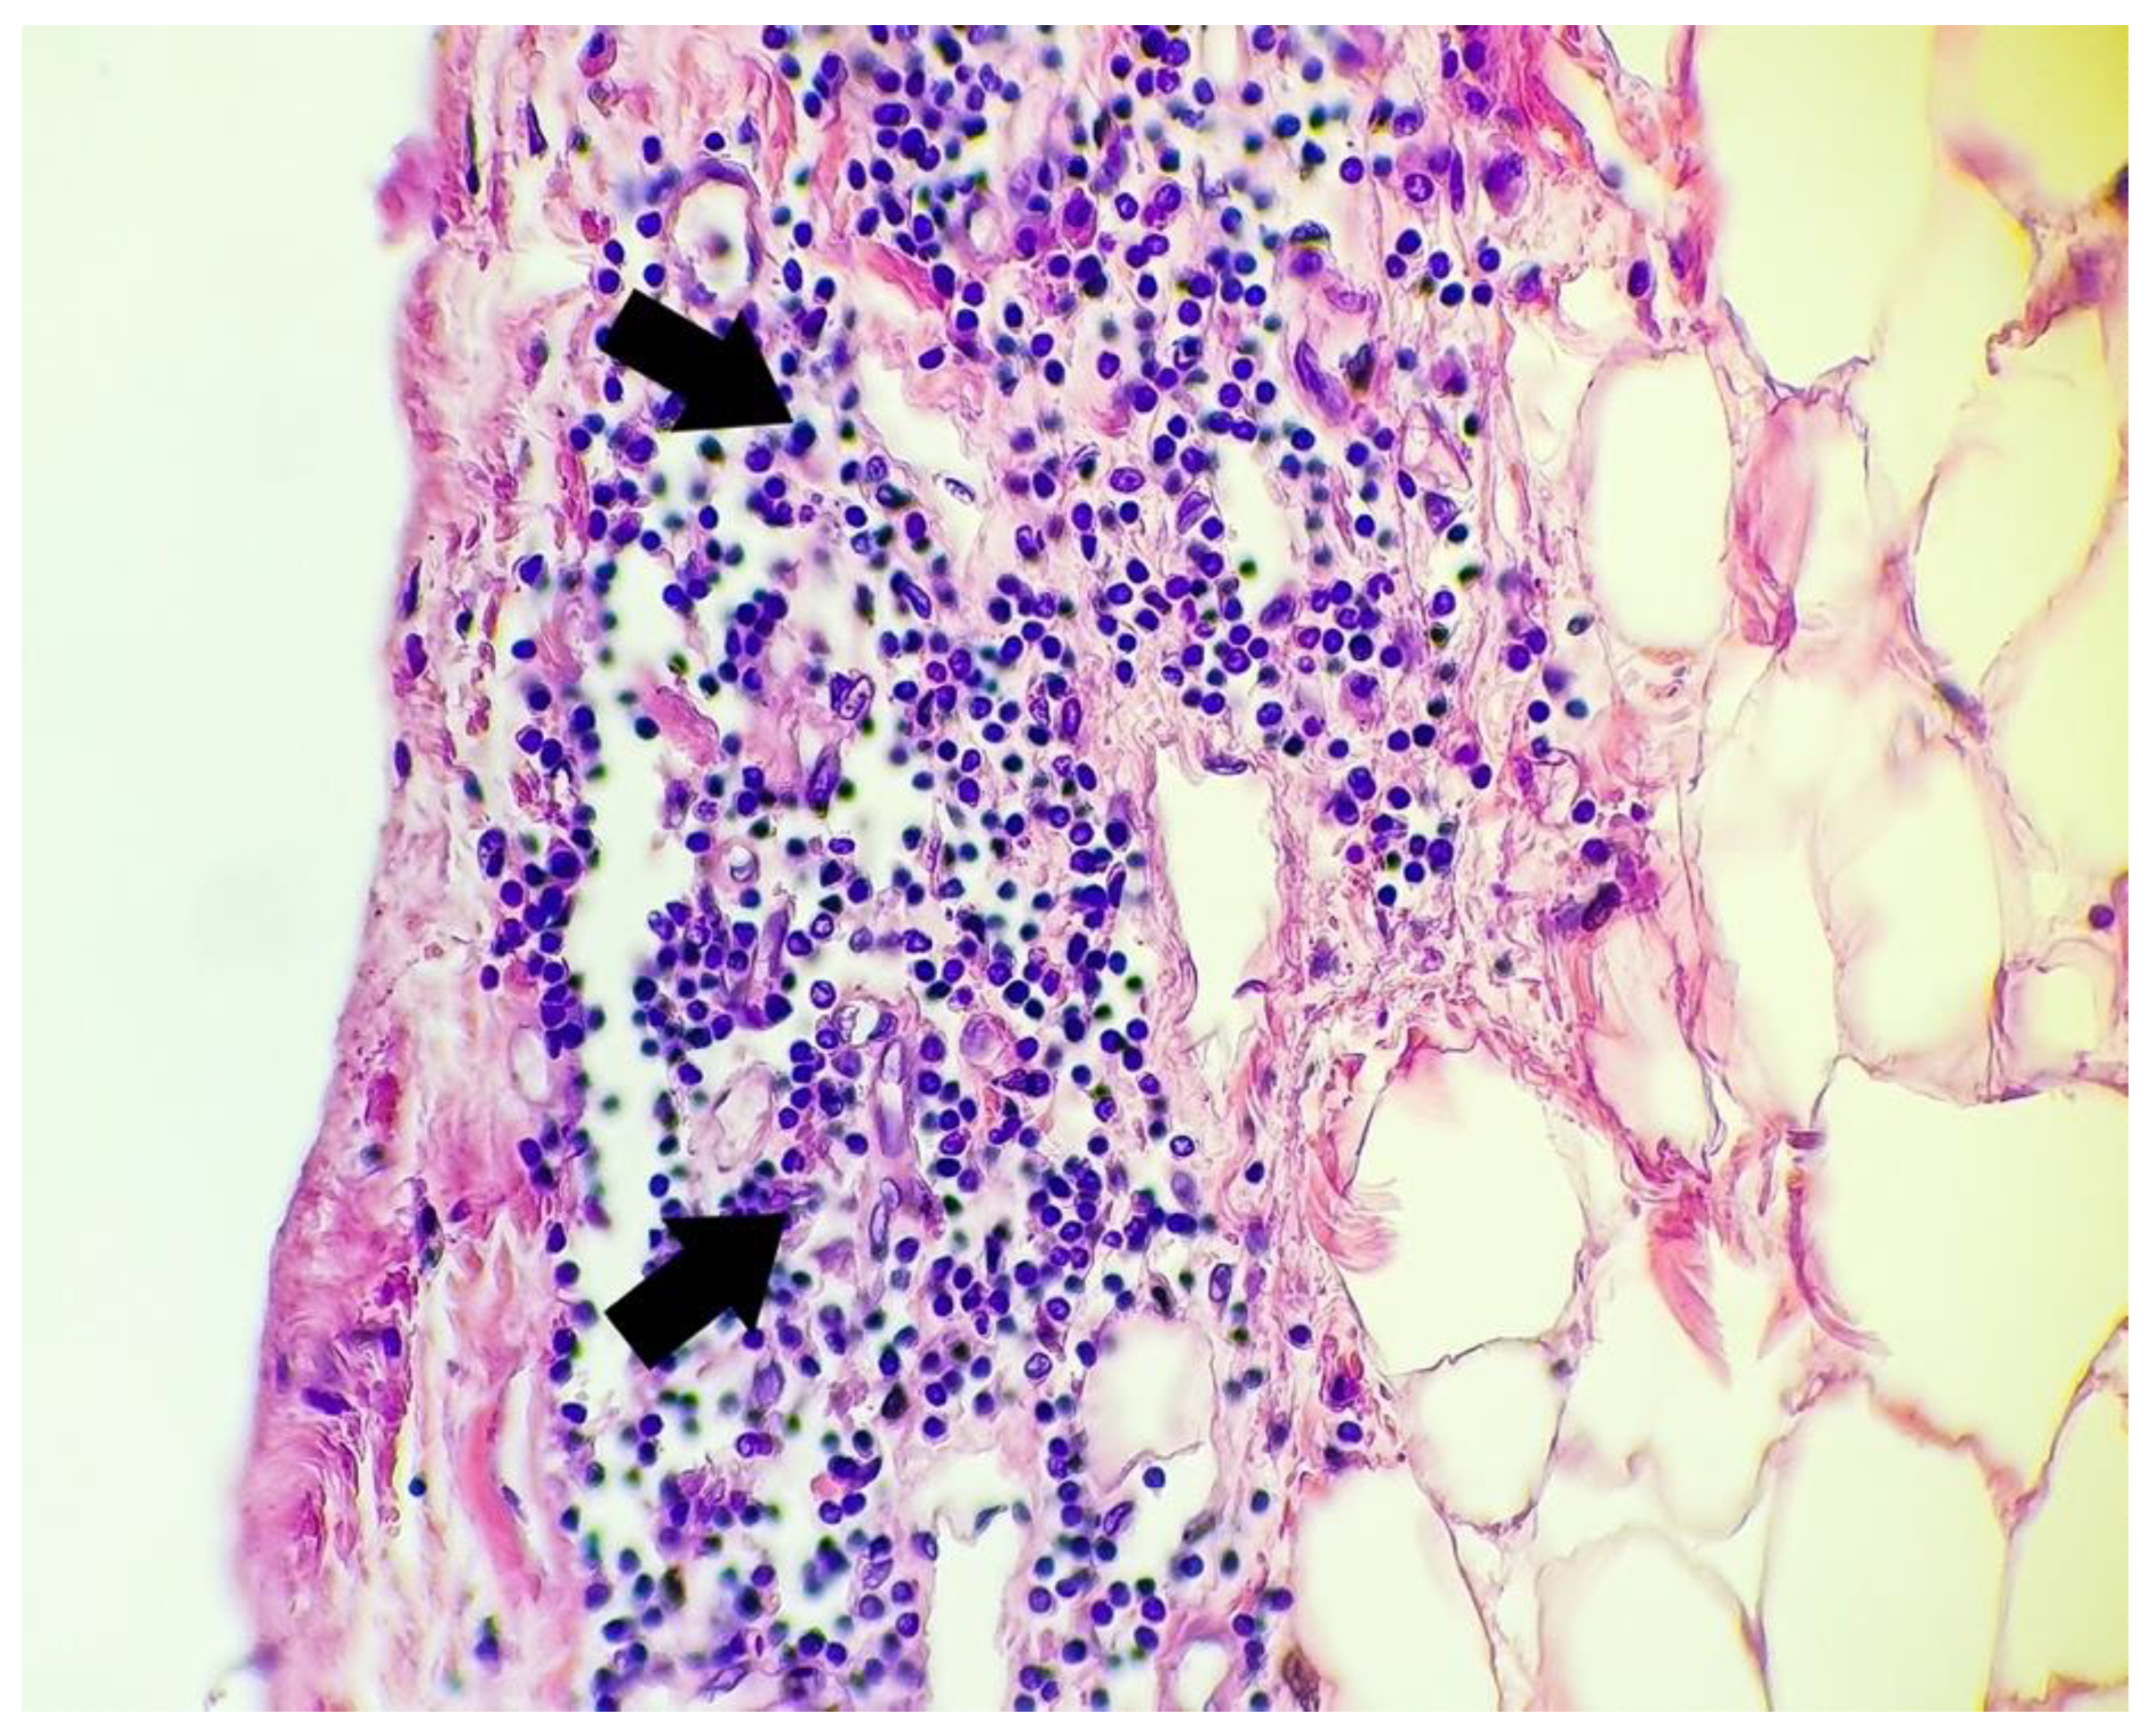

- Lymphocytic inflammatory infiltrate in the subepicardial region and/or visceral pericardium: nine cases

| Case no. 6 | Rich diffuse inflammatory lymphocytic infiltrate in the subepicardial space visceral pericardium, with focal fibrin deposits on the surface Large extended areas of fibrosis interposed between myocardial fibers, sequestrating groups or individual myocytes, with thick, poorly cellularized, horizontally-arranged collagen fibers. In these patches of fibrosis, there is a more myxoid appearance, with an increased number of blood vessels and with a perivascular scattered lymphocytic infiltrate Small, poorly-defined areas of myocardial fibers with cytoplasmic vacuolation, nuclear pyknosis, apoptosis, and necrotic debris between these fibers Undamaged myocytes near the fibrotic patches suffered nuclear enlargement, with irregular borders and granular fine dispersed chromatin, a sign of cellular suffering Severe atherosclerosis of the coronary arteries with secondary subocclusion Large area of myocardial necrosis with enucleated muscle fibers, eosinophilia, extravasated erythrocytes, scattered lymphocytes and neutrophils and necrotic debris, with a halo of granulation tissue composed of newly-formed capillaries, macrophages, and lymphocytic infiltrate |

| Case no. 15 | Rich diffuse lymphocytic infiltrate in the subepicardial region Fibrosis bands between groups of myocardial fibers Scattered small number of lymphocytes in the perivascular region |